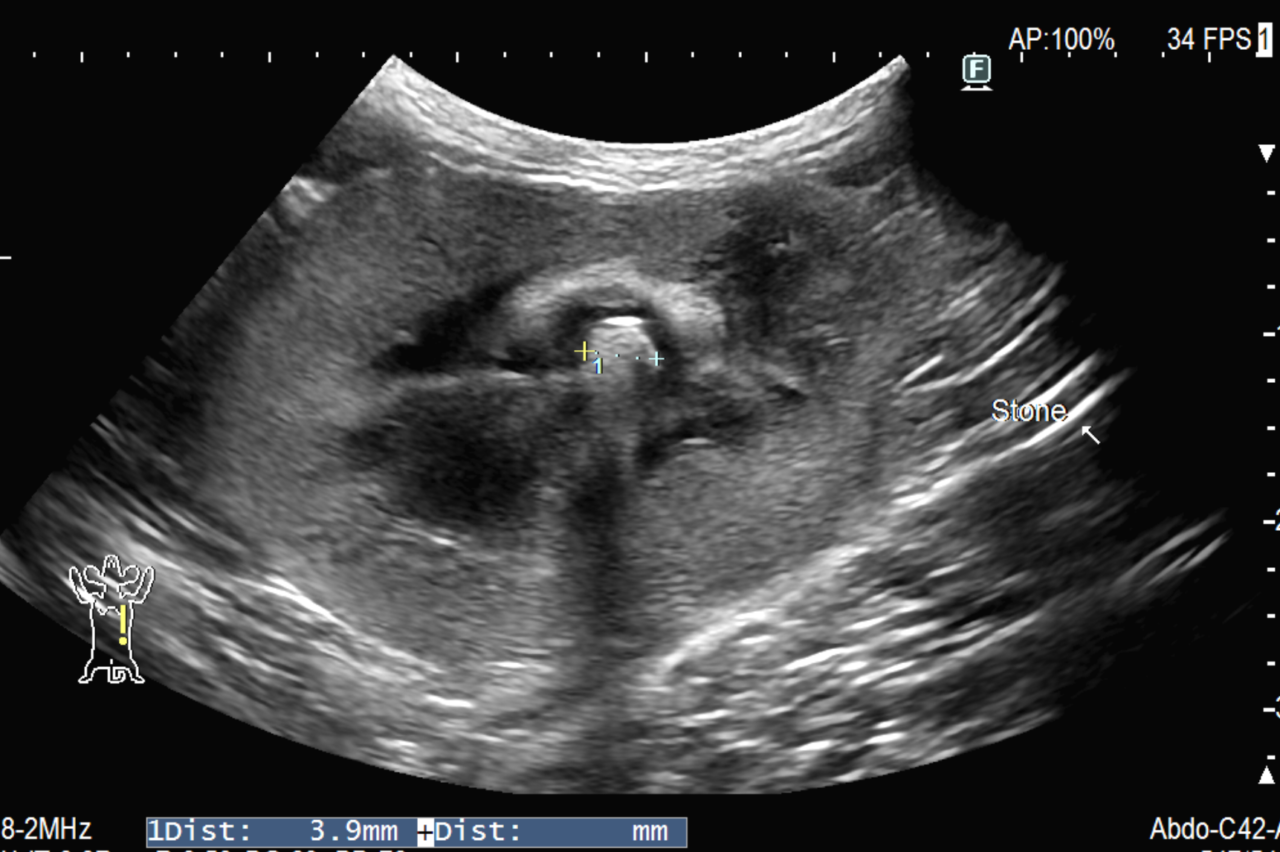

猫が尿路結石により排尿障害を起こしており、緊急の手術が必要とのことでご依頼を受けました。検査では右の腎盂・尿管が拡張しており、腎臓内に結石が認められます。鎮静下でCT撮影を行い、右尿管内に1mm程度の小さな石があることを確認できました。通常1mm程度の石であれば内科治療で膀胱へ流れてくれることが多いのですが、注意しなければいけないのは背景疾患です。腎盂穿刺を行い、腎盂尿を採取すると膿のような尿が採取されました。顕微鏡検査を行うと菌(大腸菌)が確認され腎盂腎炎と診断しました。幸い抗生剤が効く菌であり、数日の入院ののちに元気になり退院してくれました。1ヶ月検診でも尿の流れは問題なくかかりつけ医にお戻りいただいています。